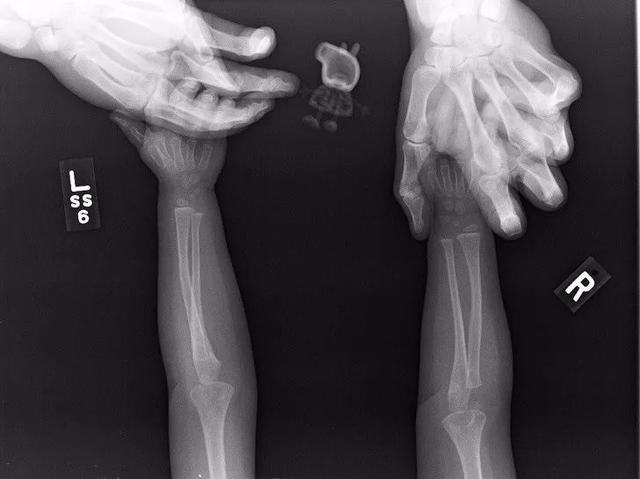

六根手指的X光图